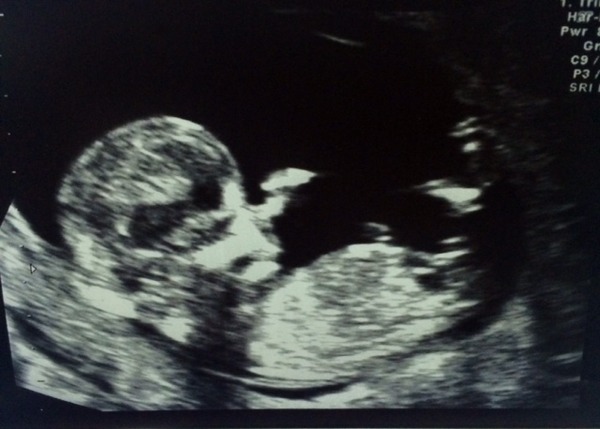

Lindalove · 22/09/2014 14:59

Hi yes scan attached - baby had his hand in front of his nose, so that's no a massive nose honest! My new EDD is April 2 rather than April 4, so much of a muchness really.

Its really amazing to see the development from 8 weeks - I could see ribs, eyes, fingers.... pretty sure he/she hiccupped a few times as well.